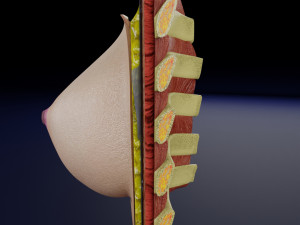

This is a 1:1 scaled model of right breast cut opened in sagittal plane to reveal its internal antomy and histology (schematic). The deeper parts and fascial layers are also depicted to give a very detailed approach to the model. The full layers starting from skin, nipple areola, till intercodtal muscles and ribs are also depicted.